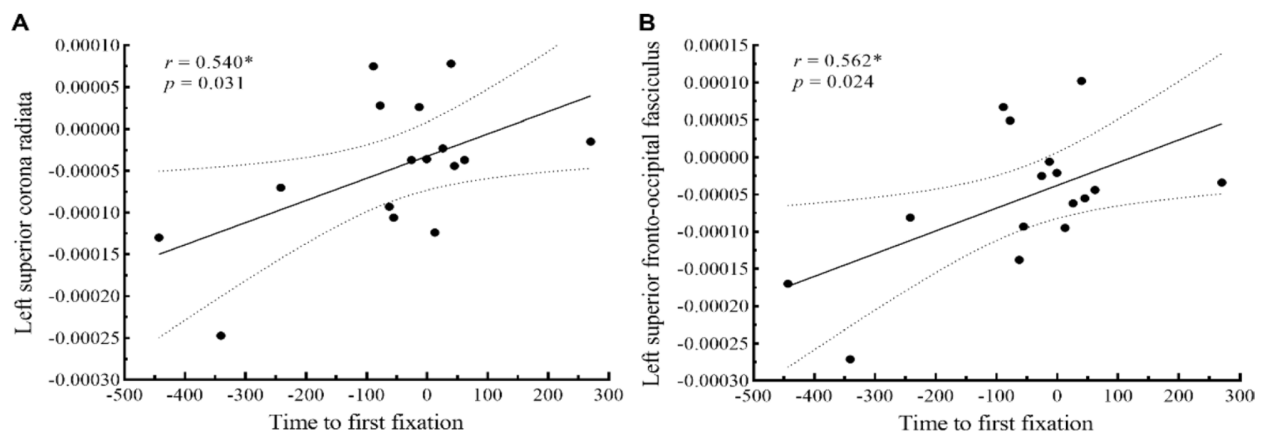

此外,研究结果发现,实验组儿童所发现的减少的首次注视时间与降低的左侧上放射冠和左侧上额枕束平均弥散率呈显著正相关。这表明,篮球运动技能干预有效改善了孤独症儿童的共同注意力,其改善机制可能与感觉感知、空间和早期注意功能相关的白质纤维完整性变化有关。

图2. 实验组干预前后白质平均弥散率变化值与眼动指数变化值的关系